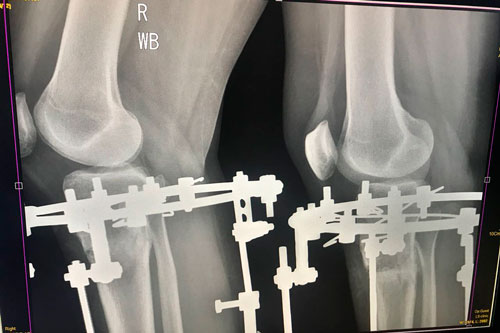

Исходник 33 года.

Дата операции 26.04.2018г.

Перед крутками